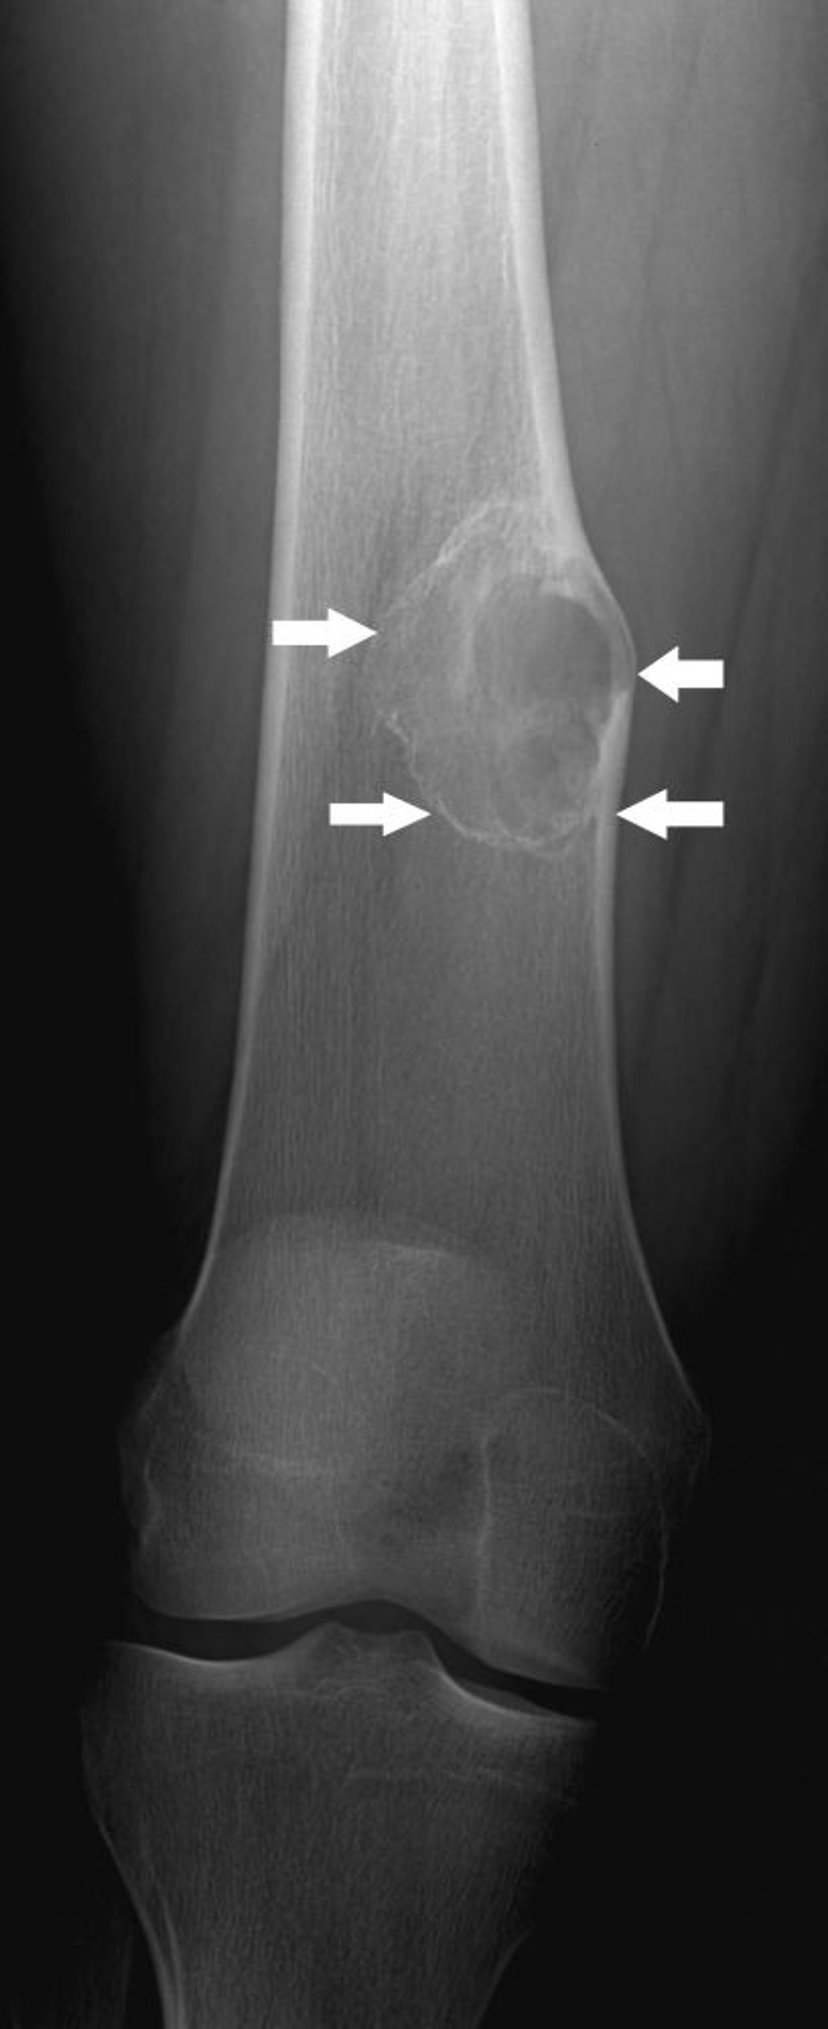

Fibroma no osificante

Esta radiografía muestra una lesión ósea (flechas) en el fémur por encima de la rodilla con expansión leve, que es característica de un fibroma no osificante.

Image courtesy of Michael J. Joyce, MD, and Hakan Ilaslan, MD.